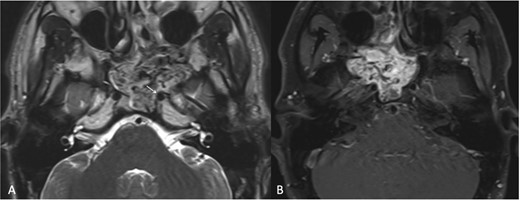

A 23-year-old patient presented with left-sided recurrent epistaxis, occipital headache, and nasal obstruction. MRI revealed a hypervascular soft tissue mass measuring 5.1 × 4.5 × 4.7 cm in the posterior aspect of the nasal cavity, with complete obliteration of the left sphenoid sinus (Fig. 3a). The tumor extended laterally into the pterygopalatine fossa, reaching the level of the pterygomaxillary fissure. Post-contrast T1-weighted MRI confirmed marked thinning of the lateral sphenoid wall and abutment of the left ICA (Fig. 3b). The bulk of the blood supply to the tumor was from the left IMA and was successfully embolized.

(a) Transaxial T2-weighted MRI image showing a mass with heterogeneous signal intensity and multiple flow voids, along with thinning of the cortical bone overlying the left ICA (arrow). (b) Post-contrast transaxial T1-weighted MRI image demonstrating avid contrast enhancement of the JNA.